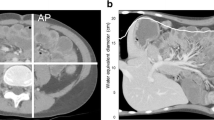

The water-equivalent diameter was derived from and automatically calculated by the dose monitoring software. It was defined as the diameter of a circle with an area equal to the image water equivalent area, i.e. the area of foreground pixels weighted according to their radiodensity compared to water. It is usually derived from the localizer, but may alternatively be derived from the axial images [22].

Chest CT examinations were divided into six different patient size groups with 4-cm water-equivalent diameter bins between 13 and 29 cm, according to Kanal et al. [20]. Minimum and maximum water-equivalent diameters were 11 cm and 35 cm, respectively. There was a strong positive, statistically significant correlation between water-equivalent diameter and CTDIvol (rs = 0.773, P < 0.001) and water-equivalent diameter and DLP (rs = 0.802, P < 0.001). Scatterplots of water-equivalent diameter against CTDIvol and against DLP are shown in Fig. 1 (CTDIvol) and Fig. 2 (DLP). Box plots demonstrate the distribution of water-equivalent diameter according to patient age groups (Fig. 3), showing wide ranges, especially in the age group of 10- to 15-year-old children. Most examinations were in patients of size 17 cm to under 21 cm (n = 211 [39%]). Sample sizes and distribution of age and gender within patient size groups are given in Table 3.